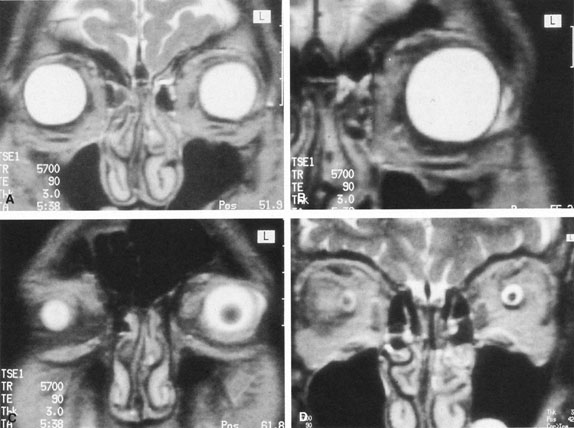

The ciliary ganglion is an irregular structure, measuring 1 mm by 2 mm, that lies just temporal to the optic nerve (Figs. 3 and 4), 7 to 10 mm from the orbital apex.47,51 In it the presynaptic parasympathetic fibers from the Edinger-Westphal nucleus synapse with the postsynaptic fibers that form the short ciliary nerves. Most of these fibers innervate the ciliary muscle, and the remaining 3% to 5% supply the iris sphincter. The ganglion also contains sensory branches of the nasociliary nerve and sympathetic fibers en route to the choroidal vasculature.

When attempting to provide akinesia, it should be kept in mind that the motor nerves enter the rectus muscles at the junction of their posterior and medial thirds, or more anteriorly.52 It is also important to remember that these fibers run both distally and proximally between the muscle fibers before they end at the myoneural junctions. A motor block may therefore be achieved at many points along their path. The oculomotor divisions may be blocked in the posterior orbit before their insertion into the rectus muscles, but it is necessary to keep in mind the proximity of the optic nerve, the ophthalmic vein, and the anterior muscular branches to the oculomotor branches in this region (see Fig. 3). Because the nerve and artery supplying the inferior oblique muscle insert more anteriorly, they are more vulnerable to needle trauma from peribulbar or retrobulbar blocks delivered along the floor of the orbit.48 The superior oblique muscle is innervated and receives its blood supply in the posterior orbit. Because it is relatively immobile in the superotemporal orbit, it is possible to injure this muscle with blocks in this area.

Blocks delivered in the anterior or middle orbit depend on diffusion of the anesthetic agent into either the posterior orbit, to the origin of the nerve branches, or into the muscles themselves at the point where distal branches insert into myoneural junctions. The first process is dependent on the anatomy of the connective tissue planes that subdivide the orbit into compartments (see Fig. 4). This architecture varies among patients. The classic teaching of a single intermuscular septum that connects the rectus muscles and divides the orbit into an intraconal and an extraconal space is overly simplified. Histologic examination of the orbit reveals an arrangement of roughly parallel and partially broken septa of various thicknesses, with and without fenestrations.48 This anatomic variability, therefore, accounts for the variability in akinesia seen with orbital blocks.